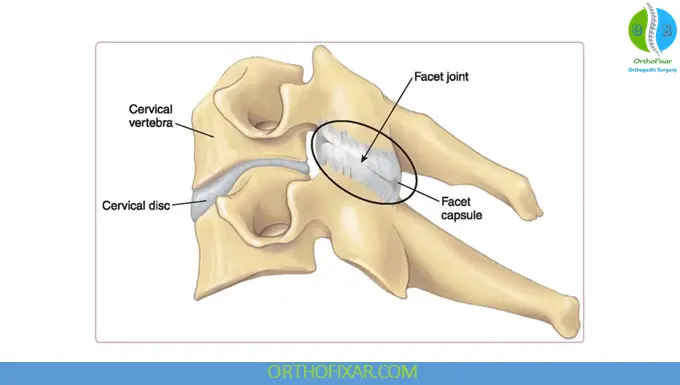

Anatomy of the Facet Joints

Facet joints (zygapophyseal joints) are synovial joints formed between the superior and inferior articular processes of adjacent vertebrae. Each spinal segment contains a pair of facet joints, allowing controlled movement while limiting excessive rotation and shear forces.

Healthy facet joints are covered with smooth cartilage and surrounded by a joint capsule. Degeneration of these structures leads to arthrosis and inflammation.